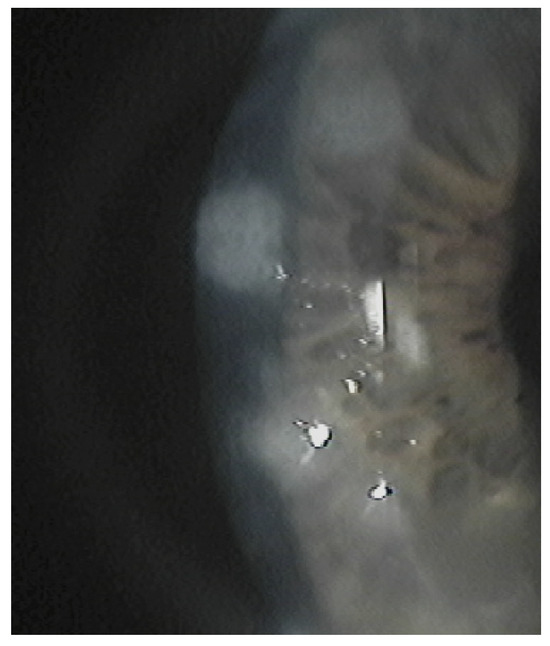

5. Clinical Signs and Symptoms

The subepithelial elevated nodules of the disease are gray-white or blue-white, and they often present in a roughly circular configuration involving the central or paracentral cornea. The nodules are typically separated by a clear cornea and are localized in the mid-periphery, and there may be only one or up to eight of them, and the nodules might be confluentin advanced stages.(Figure 1 and Figure 2). In some cases, the nodules are localized in the central cornea. This condition occurs in association with dry eye or long-standing keratitis (e.g., phlyctenulosis, trachoma, and interstitial keratitis), and the degeneration may not appear until years after the active keratitis has subsided. In extensive CL wearers, typical nodular localization at 3 and 9 o’clock has been described [5]. In about 60–68% of patients, there have been reports of symptoms such as pain, foreign body sensation, tearing and relapses in corneal erosions. In advanced stages, the most common presenting symptom is decreased visual acuity, and this is due to induced irregular astigmatism with hyperopic shift.

Figure 2. Multiple nodules.